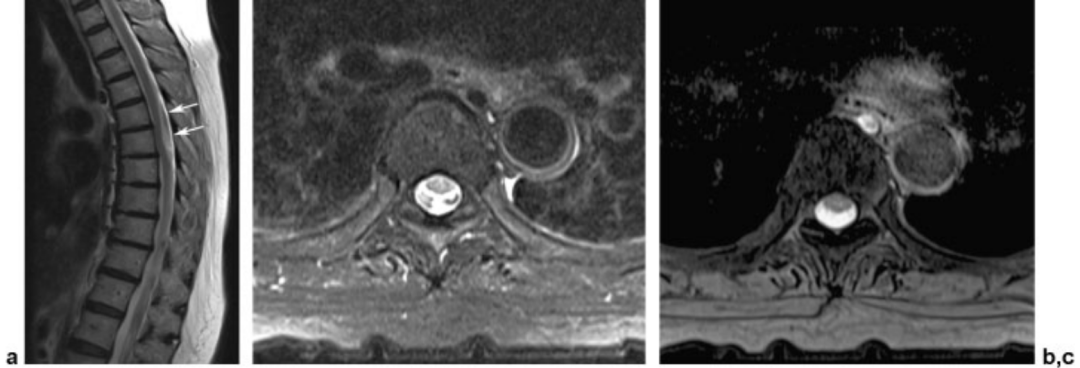

脑脊液流动伪影常易误诊为病变,需与椎管内占位相鉴别。如脊髓背侧脑脊液中可见多个不连续的低信号区,在不同序列成像中表现不同,有时可通过梯度回波 T2 加权像消除此伪影。

蓝色箭头所指的是由脊髓腔内脑脊液流动所形成的流动伪影,白色箭头所指的则是截断伪影。蓝色和白色箭头所呈现的征象均属于伪影,椎管和脊髓实际上是正常的,而星号区域为 L1 椎体血管瘤。